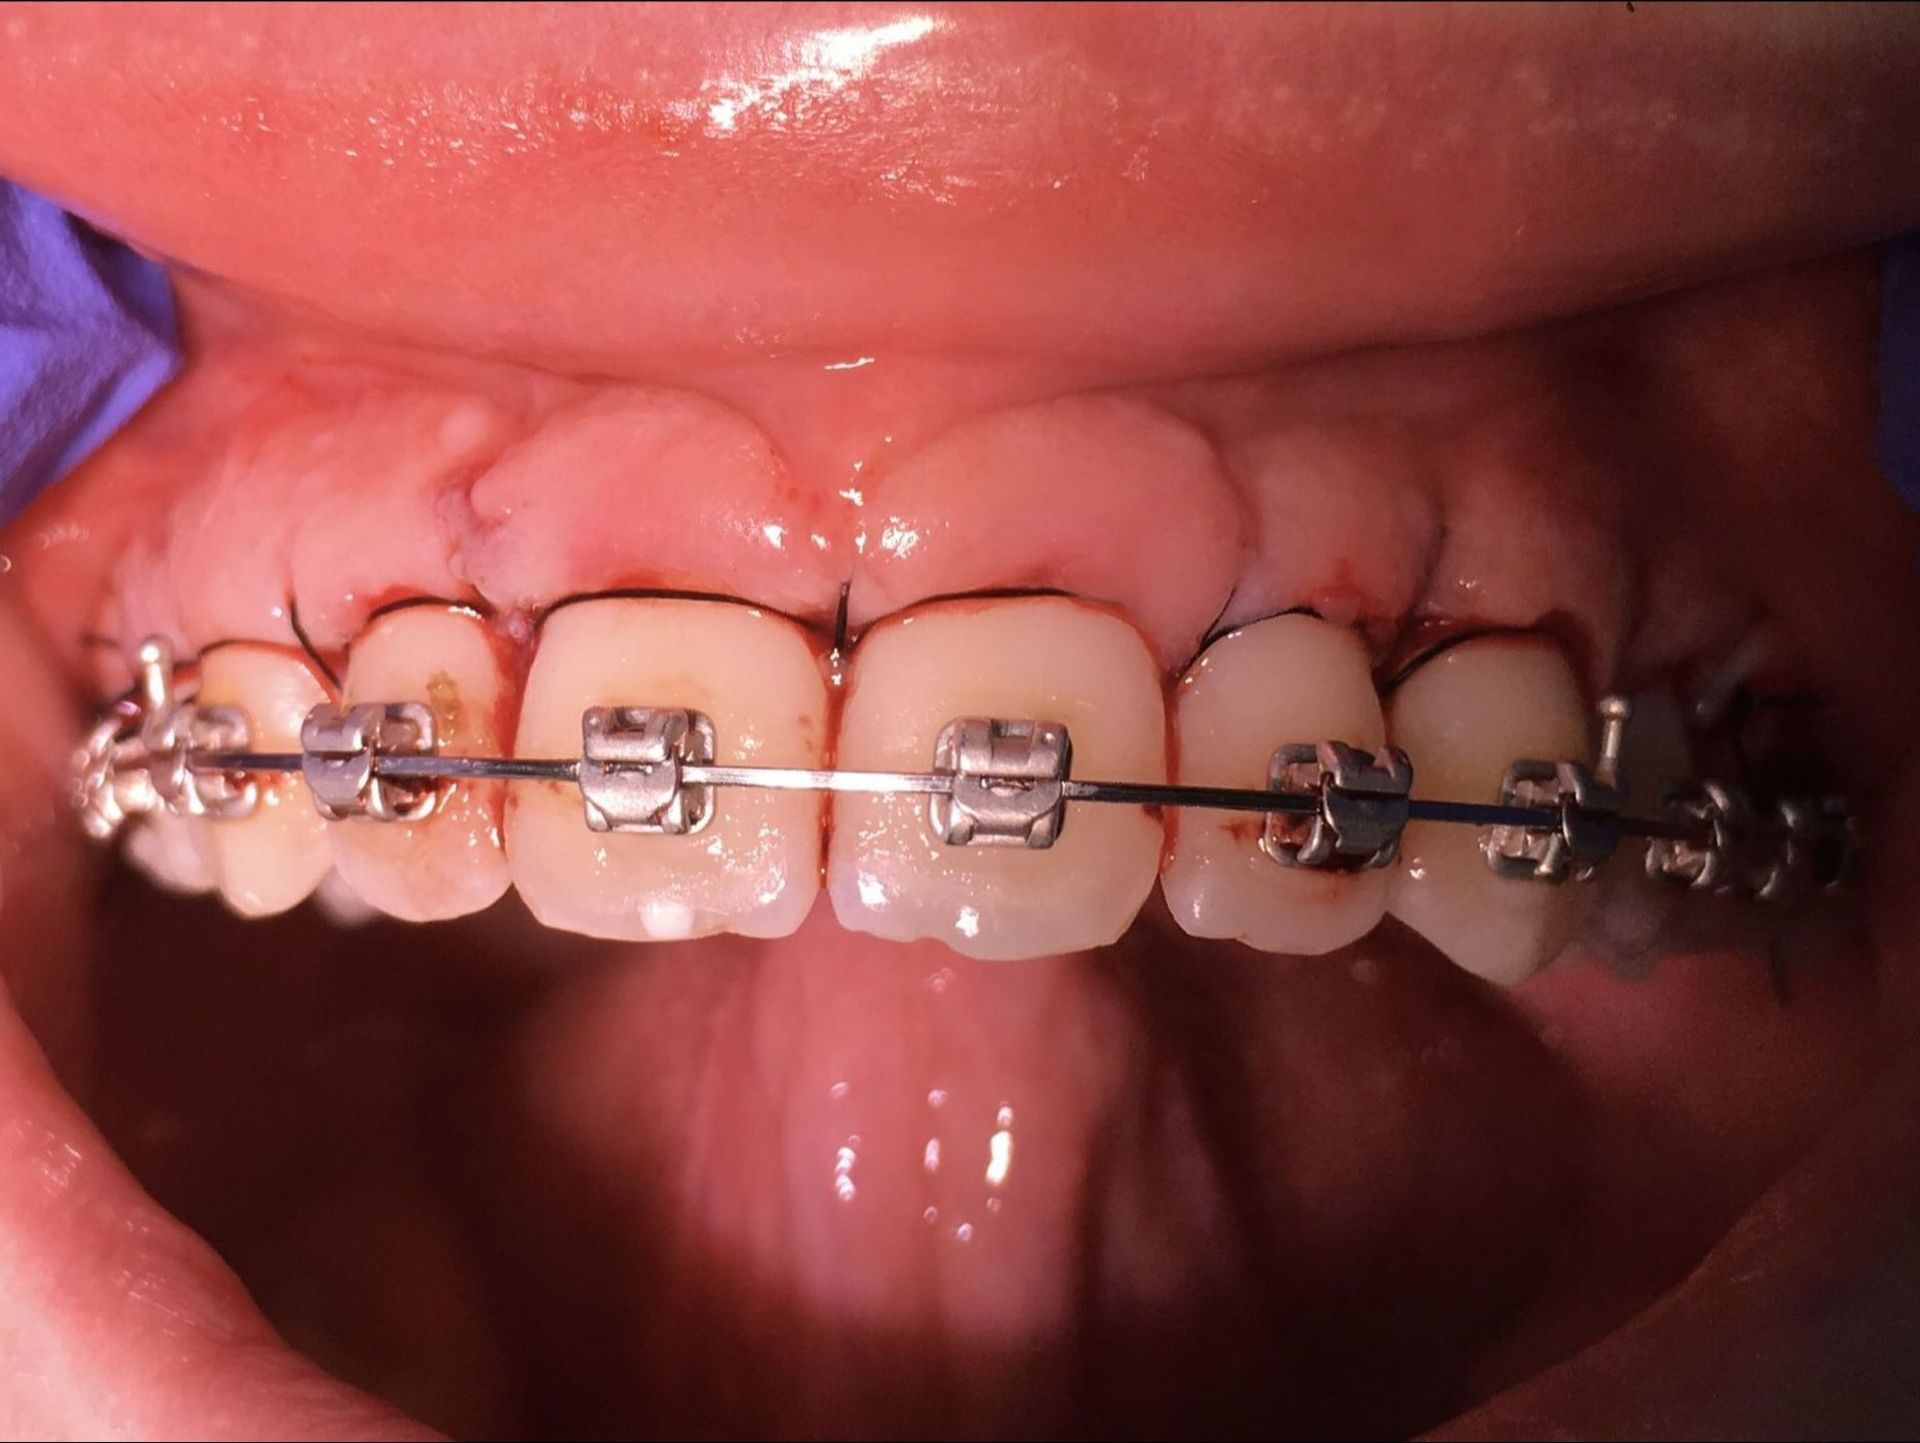

Avant et après parodontite